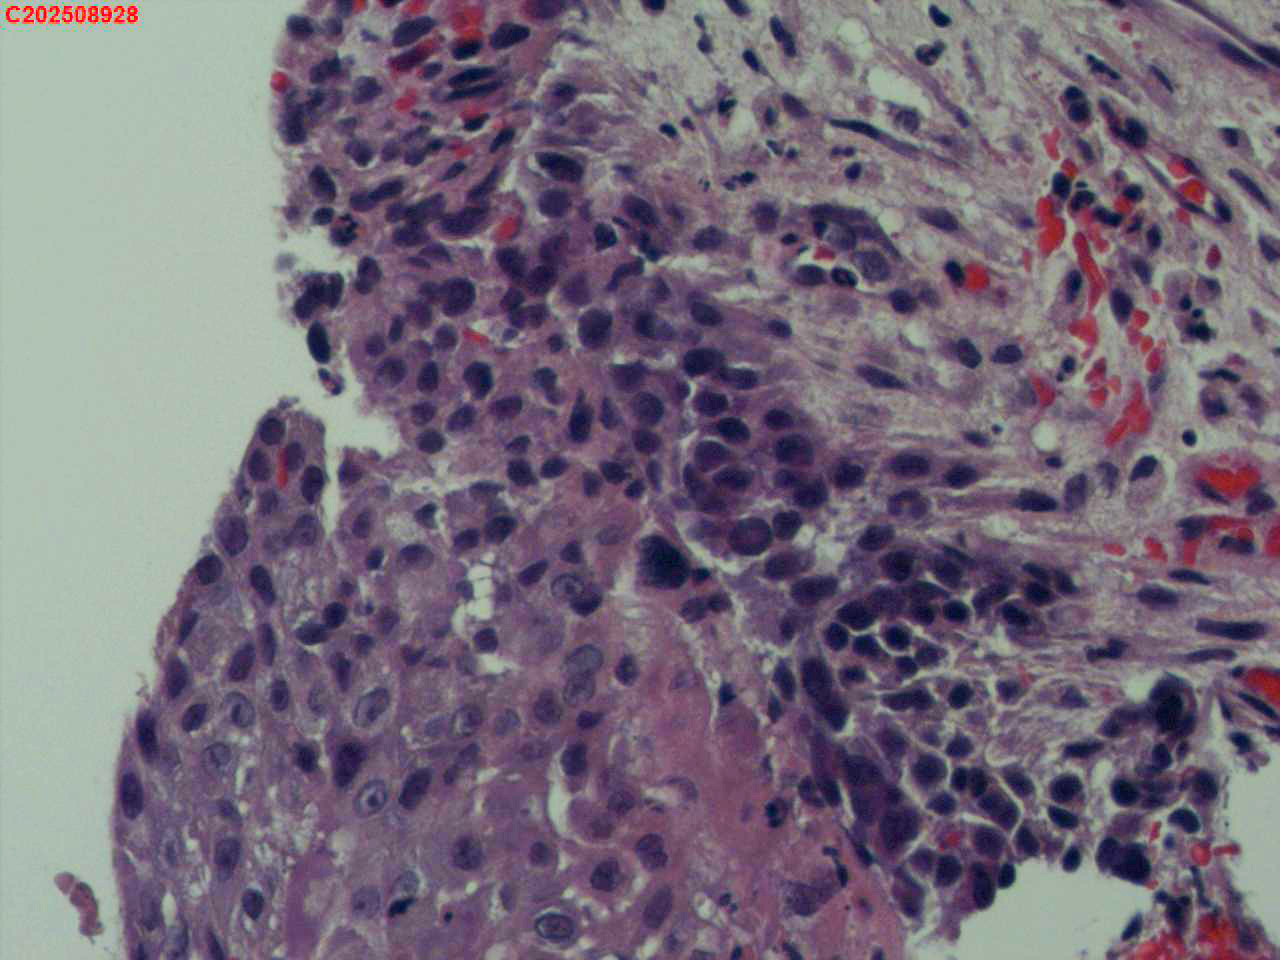

喉部右侧、声带下方咬检

喉室内右侧声带下方新生物。

考虑鳞癌

鳞癌,有微浸润